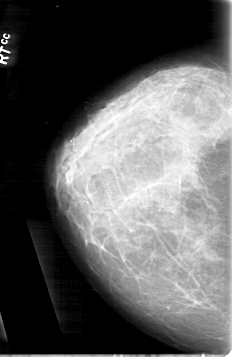

D_4092_1.RIGHT_MLO

RIGHT_CC LINES 5341 PIXELS_PER_LINE 3466 BITS_PER_PIXEL 12 RESOLUTION 43.5 NON_OVERLAY